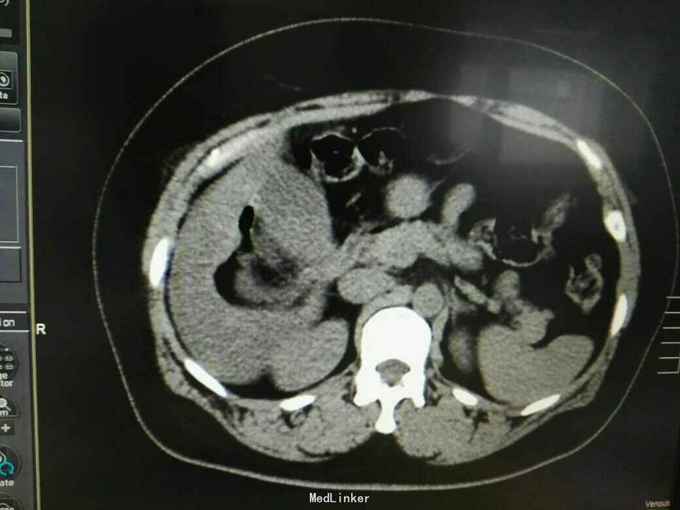

巨大肝囊肿

发现肝脏占位10年

肋弓下可触及囊性占位

肝囊肿

今日在局麻下行囊肿穿刺抽吸+无水酒精注射术 术中共抽取淡黄色液250ml